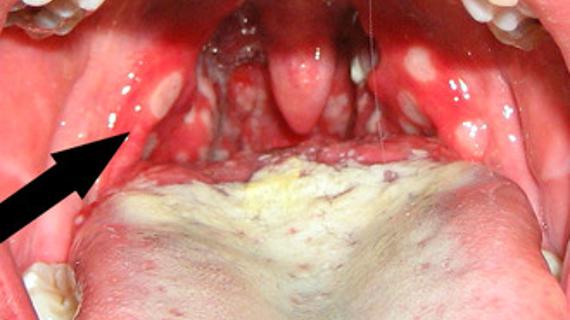

Клинические проявления грибка в горле и кандидоза миндалин. Что такое фарингомикоз? Обзор эффективных антимикотиков и антисептических средств в...

Каковы основные признаки и симптомы фарингомикоза – разновидности, формы течения и клинические проявления грибковой инфекции...